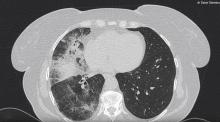

This video shows a VATS lower bilobectomy of the lung with systematic lymph node dissection for NSCLC, using a “fissure last” technique in a fissureless patient. This is a classic three-port technique with the surgeon and assistant standing in front of the patient. By avoiding dissection in the fissure, the surgeon can diminish the rate of air leakage postoperatively and reduce overall morbidity. In the author's view, length of hospital stay and hospital costs are also reduced with this technique.